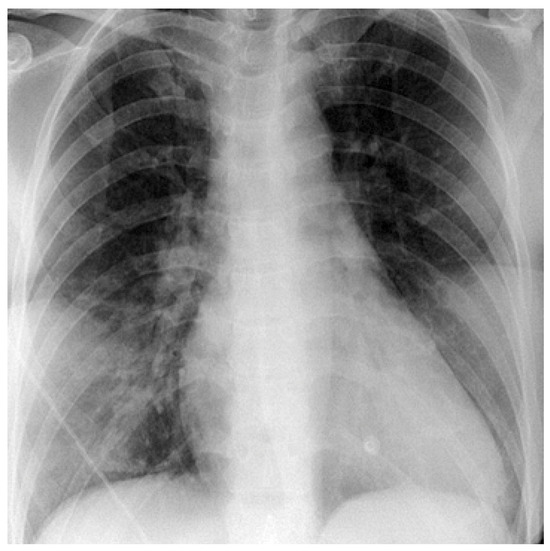

Atrial fibrillation is a cause of left atrial thrombus leading to cardioembolic stroke, which can be effectively prevented with oral anticoagulation. Right atrial appendage thrombus is a rare complication of atrial fibrillation that can also lead to cardioembolic pulmonary embolism. We present the case of a 71-year-old male with atrial fibrillation, thrombus in the right atrial appendage and pulmonary embolism. Full article

Show Figures

Figure 1